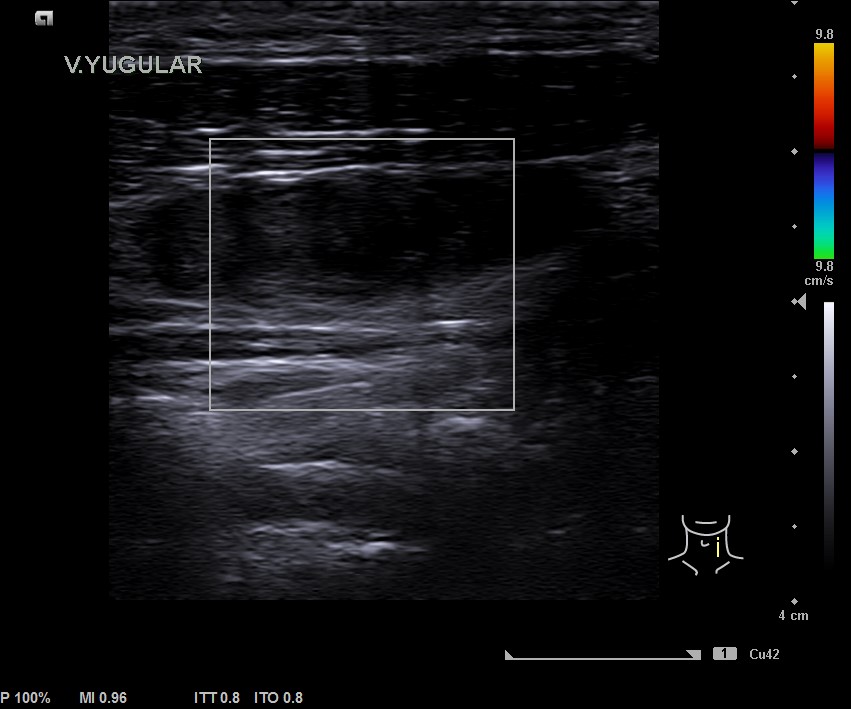

En la ecografía tiroidea se observa en LTI nódulo de 10 mm de bordes mal definidos, lobulado, mayormente sólido, más alto que ancho, isoecogénico, halo periférico hipoecoico, vascularización difusa, que sugiere TIRADS 5. Ausencia de flujo en Vena yugular interna izquierda, ensanchada, que sugiere trombosis yugular aguda o subaguda y junto a ella, posible conglomerado adenopático.